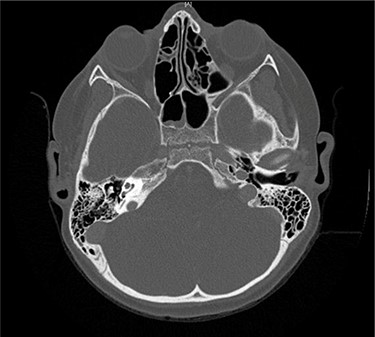

Serial MRIs were conducted following discharge. MRI at 1 month showed a contrast-enhancing mass in the right internal auditory canal with enhancement of the right petrous apex and associated labyrinthitis. An MRI at 2 months showed persistence of the lesion, whereas computed tomography (CT) showed new osseous erosion and irregular lucency within the posterior cortex of the petrous apex (Figs 1 and 2). Given the patient’s hearing loss, persistence of the lesion and concern for neoplasm, surgical intervention was recommended to the family. Surgery was initially deferred, and serial imaging was recommended. The facial nerve palsy resolved and patient was followed closely as outpatient with family reluctant to pursue surgical intervention. However, repeat imaging at 4 months after the initial encounter demonstrated persistence of the lesion, and the family consented to surgery.

Axial contrast-enhanced T1-weighted image taken 3 months after admission shows enhancement within the right petrous apex and anterior aspect of the internal auditory canal.